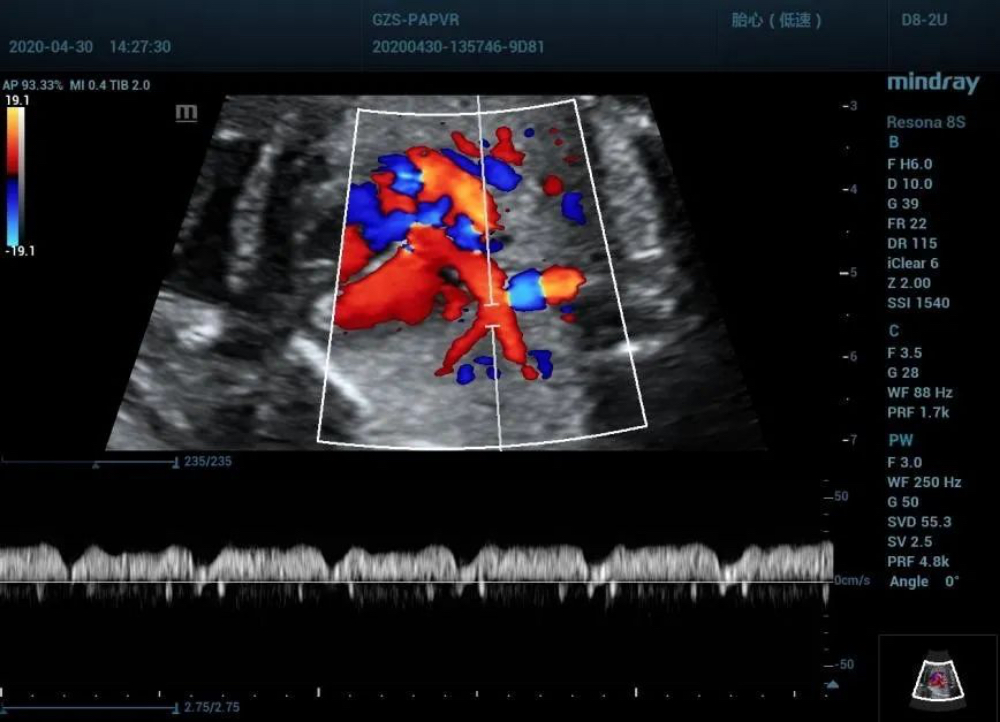

Pulmonary vein spectrum (left inferior pulmonary vein)

Observe pulmonary venous returning at low-level four-chamber view

• Low-level four chamber view shows LSPV and LIPV return to the coronary sinus that makes the posterior wall of the coronary sinus protruded and inner diameter broadened.

• Color Doppler shows the blood from LSPV and LIPV flowed through the coronary sinus and directly flowed into the right atrium, which crossed the right superior and right inferior pulmonary veins in a dislocation rather than confluence.

• Normalization of left lower pulmonary vein spectrum.LIPV connected directly with the right atrium by the dilated coronary sinus. While during the cardiac cycle, the pressure changes in the right atrium can be transmitted to the pulmonary vein which prone to jump to conclusions.